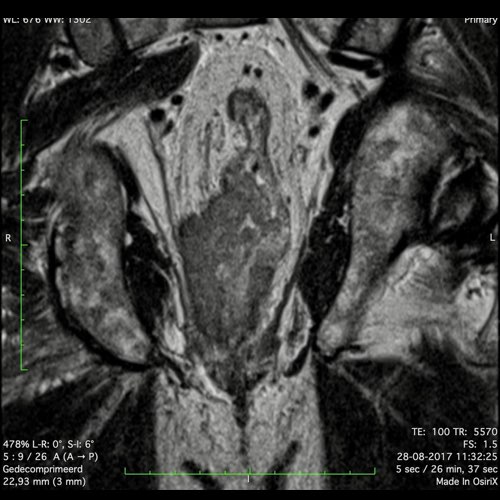

Hình ảnh

Các hình ảnh được cung cấp cho thấy ung thư biểu mô tế bào nhẫn với tình trạng dày lan tỏa thành trực tràng, hình ảnh bia bắn điển hình, và sự xâm lấn mỡ mạc treo trực tràng.